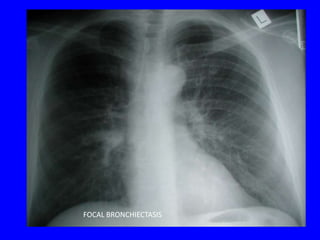

FOCAL BRONCHIECTASIS

Branching

tubular opacities

FOCAL

BRONCHIECTASIS

due to slow-growing